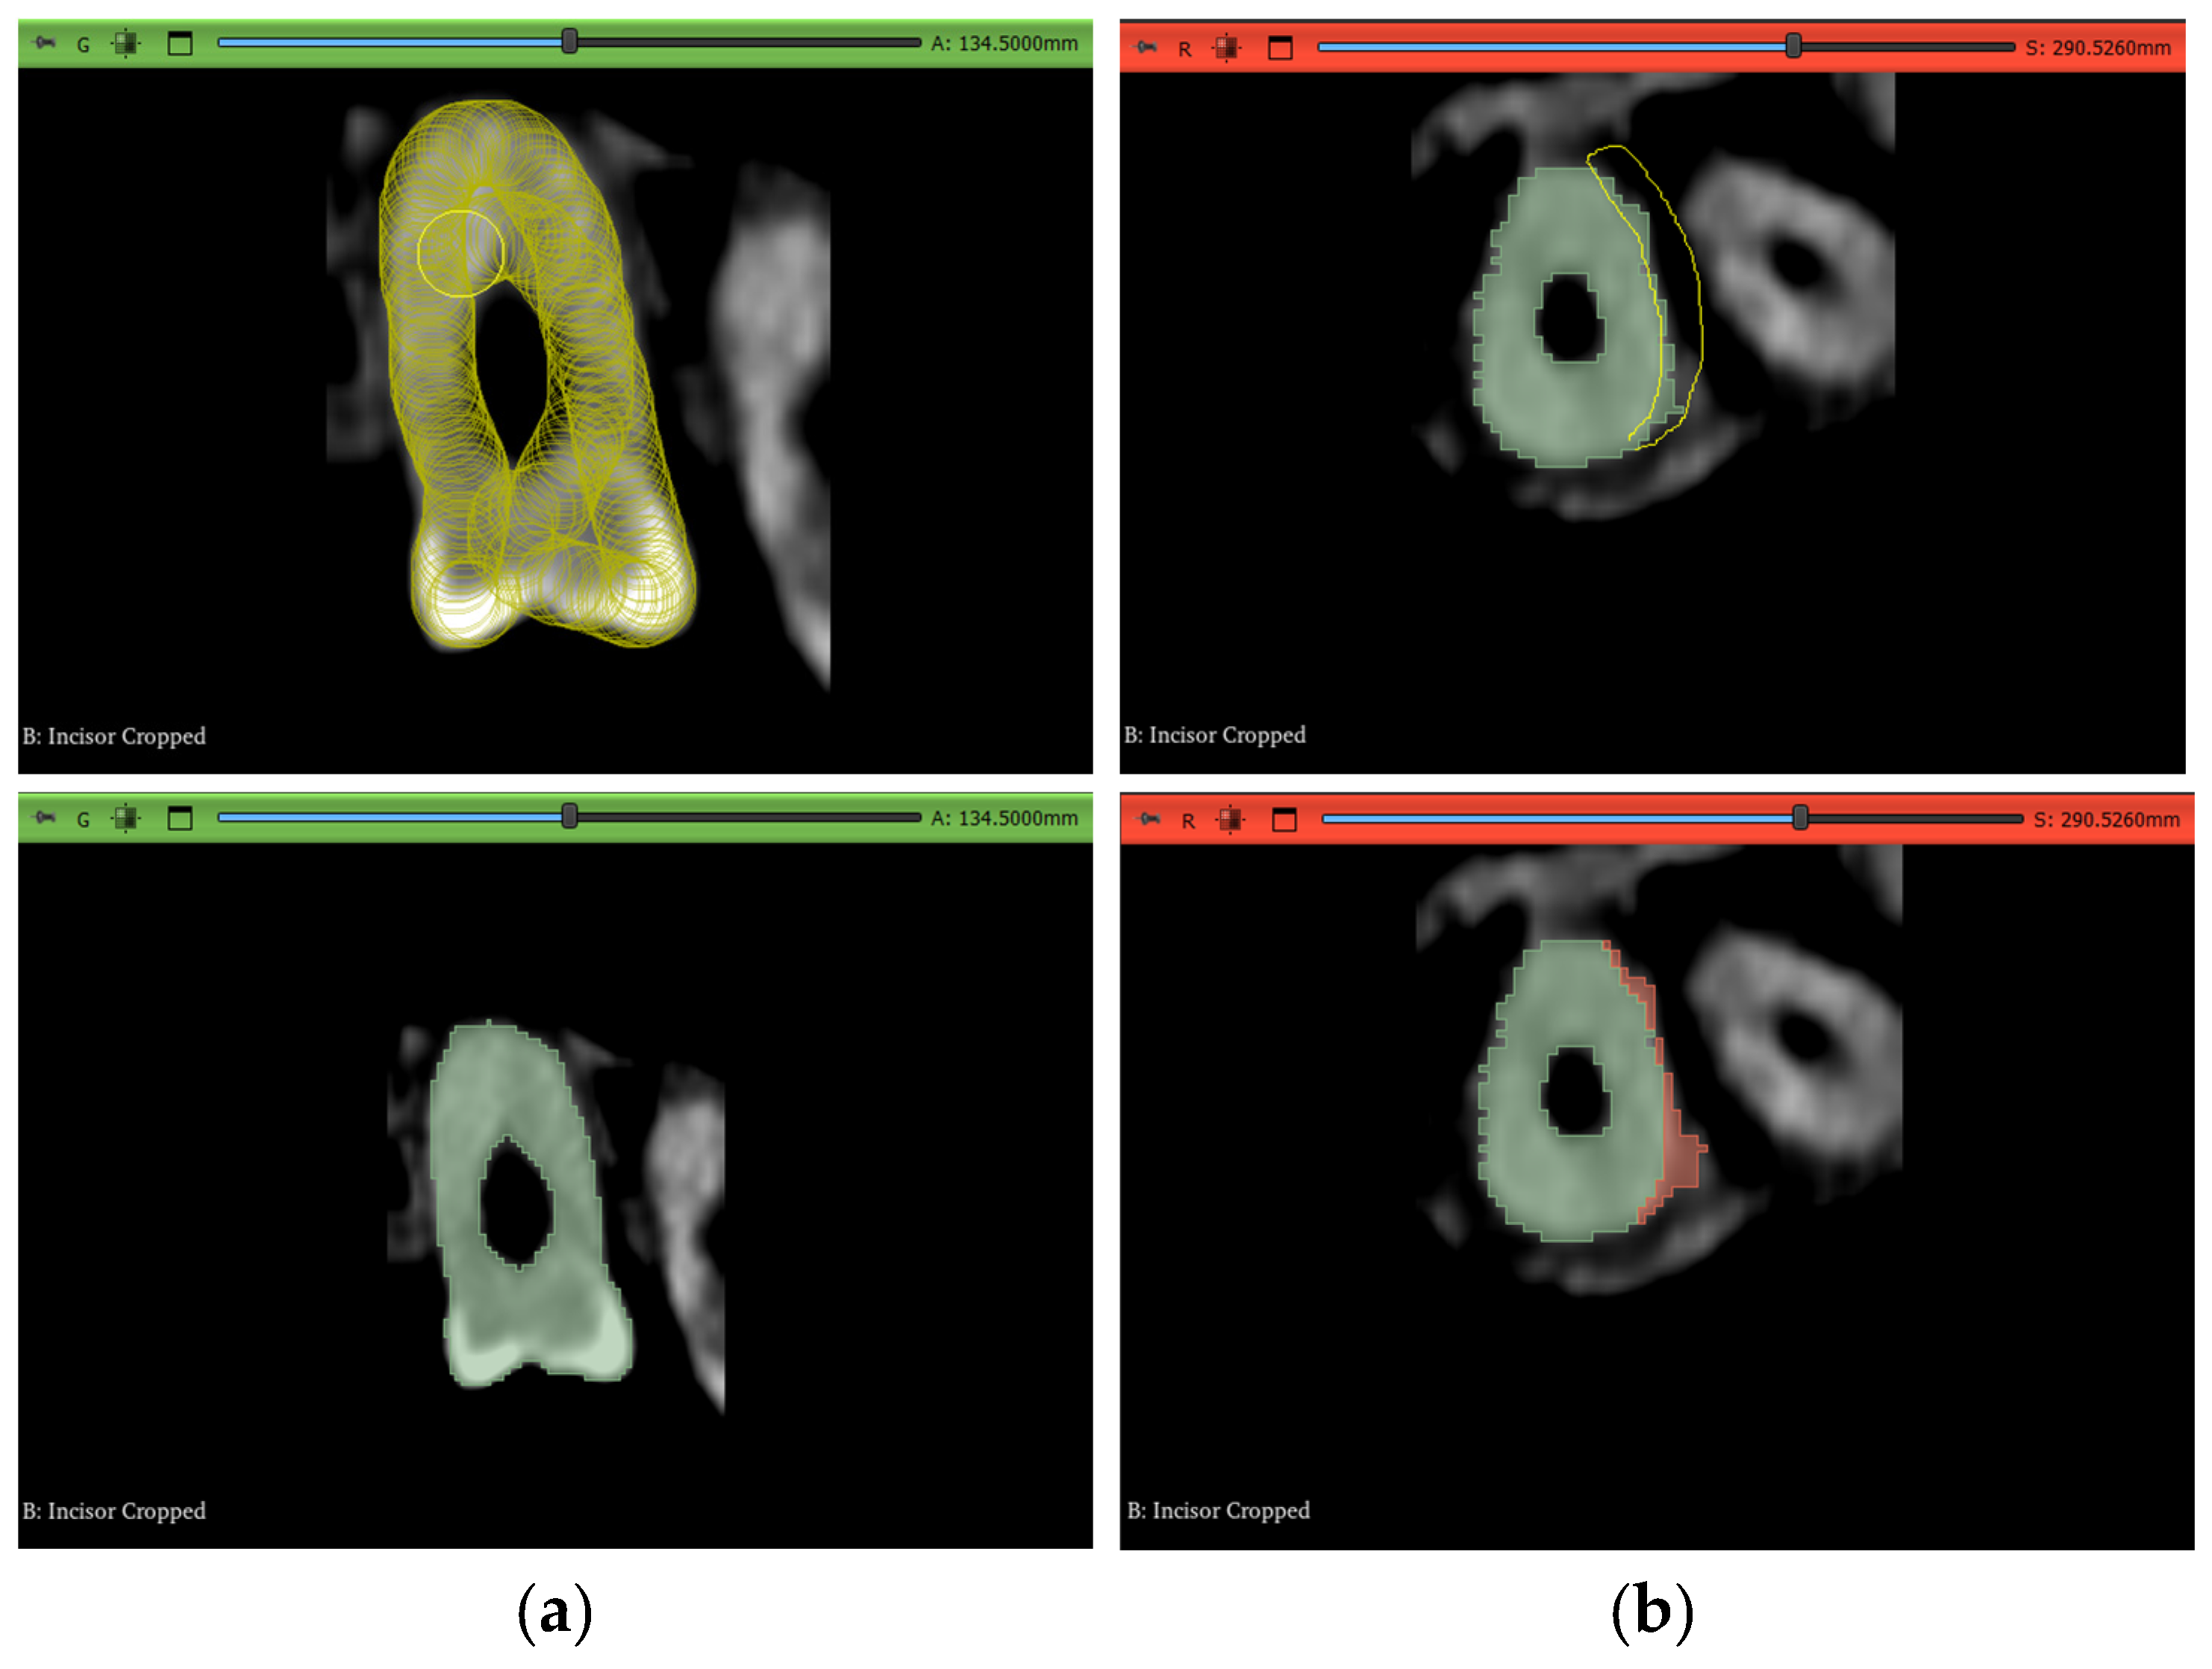

Comparisons of all models, including the manual segmentation trials, against the benchmark were performed using a dice similarity metric approach available in the “SlicerRT” extensions inside 3D Slicer [67]. Two main lines of comparison were carried out; the first comparison was a general one evaluating the overall tooth shape while accounting for the void in the pulp chamber and root canals. The second comparison was mainly focused on the accuracy of the root canals’ segmentation, since endodontics-oriented approaches are generally more challenging. This was achieved by removing the upper part of each tooth at the same level for each trial and using the subgingival part in the comparison using the same dice similarity approach; this created another 150 3D models of just the subgingival part of the teeth, bringing the total number of models in this study to 300. After the dice scores were calculated, Kruskal–Wallis tests were performed to determine whether there existed a difference in the medians between the non-manual methods and the manual method. Subsequently, Nemenyi tests were also carried out to identify which groups were significantly different from the manual segmentation method.

After obtaining the 3D models, they were separated at the same height level using a similar isolation and island removal technique as that used in Section 2.5 to cleanly cut the models from the same plane. This is shown in Figure 20 for the maxillary second molar of Dataset 2. This process yielded another 150 models for the second line of comparison regarding the subgingival part of the teeth.

Figure 20.

The method of splitting the model to obtain the subgingival part: (a) erasing on layer in the transverse plane and (b) the ouput of erasure to split the model in the sagittal plane.